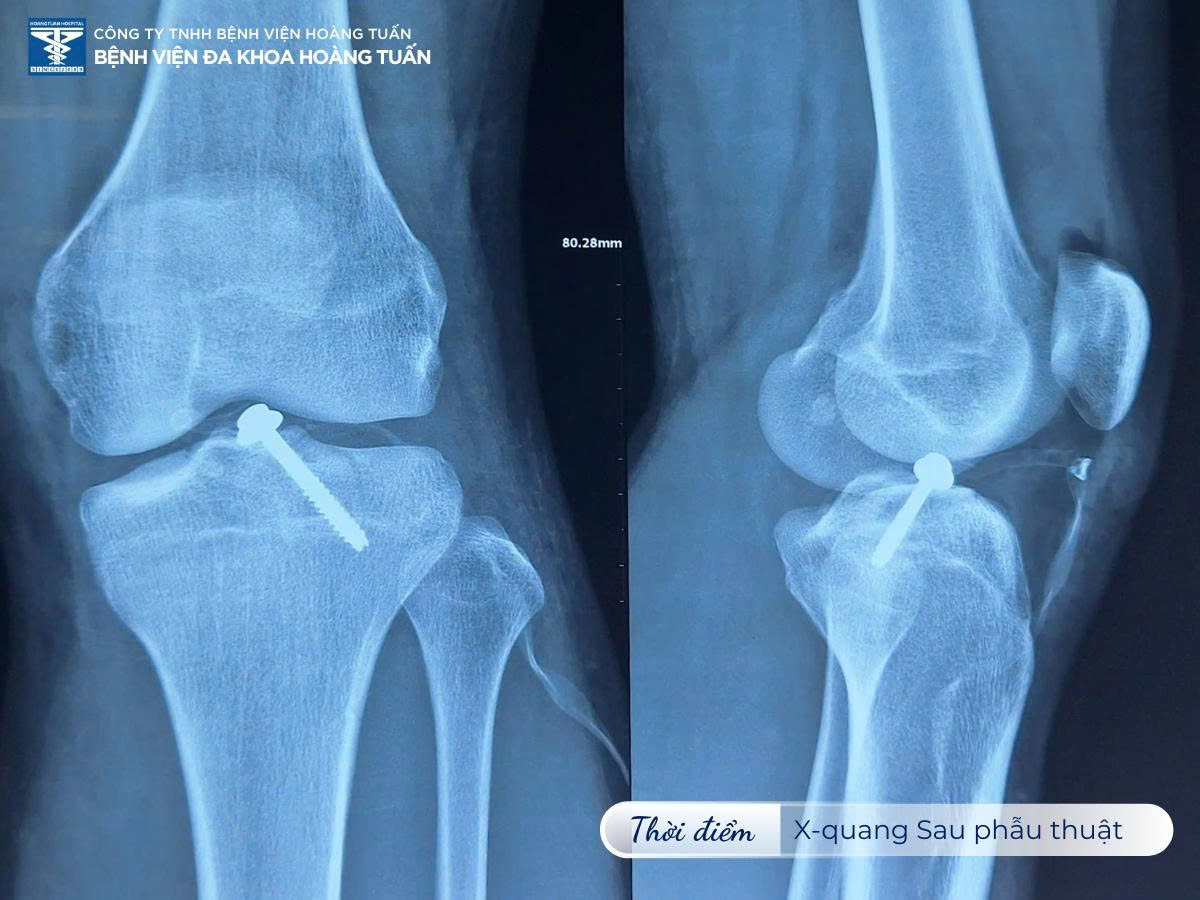

Qua thăm khám, nhận định tình trạng bệnh và chỉ định chụp X-quang kiểm tra. BSCKI. Vũ Quốc Dũng – Khoa Ngoại CTCH Bệnh viện Đa khoa Hoàng Tuấn ghi nhận bệnh nhân có biểu hiện bong điểm bám dây chằng chéo trước vùng gối trái. Bệnh nhân được tư vấn thực hiện phương pháp phẫu thuật đính điểm bám dây chằng gối trái bằng dụng cụ chuyên sâu. Đây cũng là phương pháp tối ưu nhất nhằm đưa các tổn thương về tình trạng giải phẫu ban đầu, tránh các biến chứng do bất động lâu và nguy cơ thoái hóa dây chằng khớp gối.

Ca phẫu thuật nhanh chóng được tiến hành do BSCKI. Vũ Quốc Dũng – Khoa Ngoại CTCH Bệnh viện Đa khoa Hoàng Tuấn cùng ekip phẫu thuật trực tiếp phụ trách. Sau mổ bệnh nhân giảm đau, có thể cử động tại chỗ và tập vật lý trị liệu phục hồi sớm.